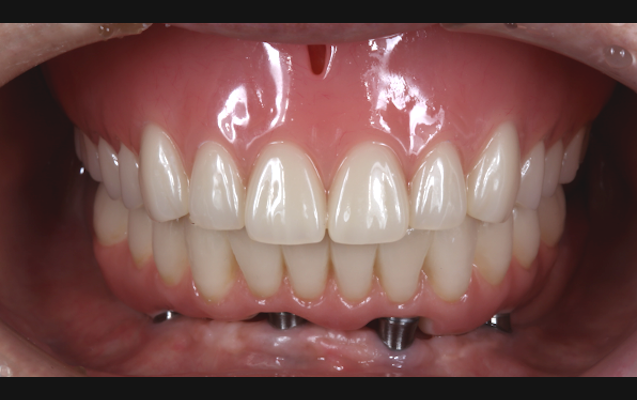

さらに、抜歯直後の歯ぐきの形を活かせるため、特に審美性が求められる前歯部では、自然な仕上がりが期待できるという利点もあります。歯がない期間を極力短くできるため、見た目や会話などに不安を抱える方にも安心してお選びいただけます。

「早く治療を終えたい」「通院回数を減らしたい」「歯がない期間を作りたくない」といったご希望に対し、身体にも心にも優しい選択肢としてご提案できるのが、この抜歯即時埋入です。

大杉歯科医院では、これまで他院で「治療が難しい」とされた症例にも真摯に向き合い、再生療法や即時埋入といった先進技術を用いて新たな選択肢をご提示してきました。

患者さまの「もう一度しっかり噛めるようになりたい」「笑顔に自信を持ちたい」といった想いに寄り添い、最適な治療方法を対話と診断を通して一緒に導き出す――それが、当院の変わらぬ姿勢です。